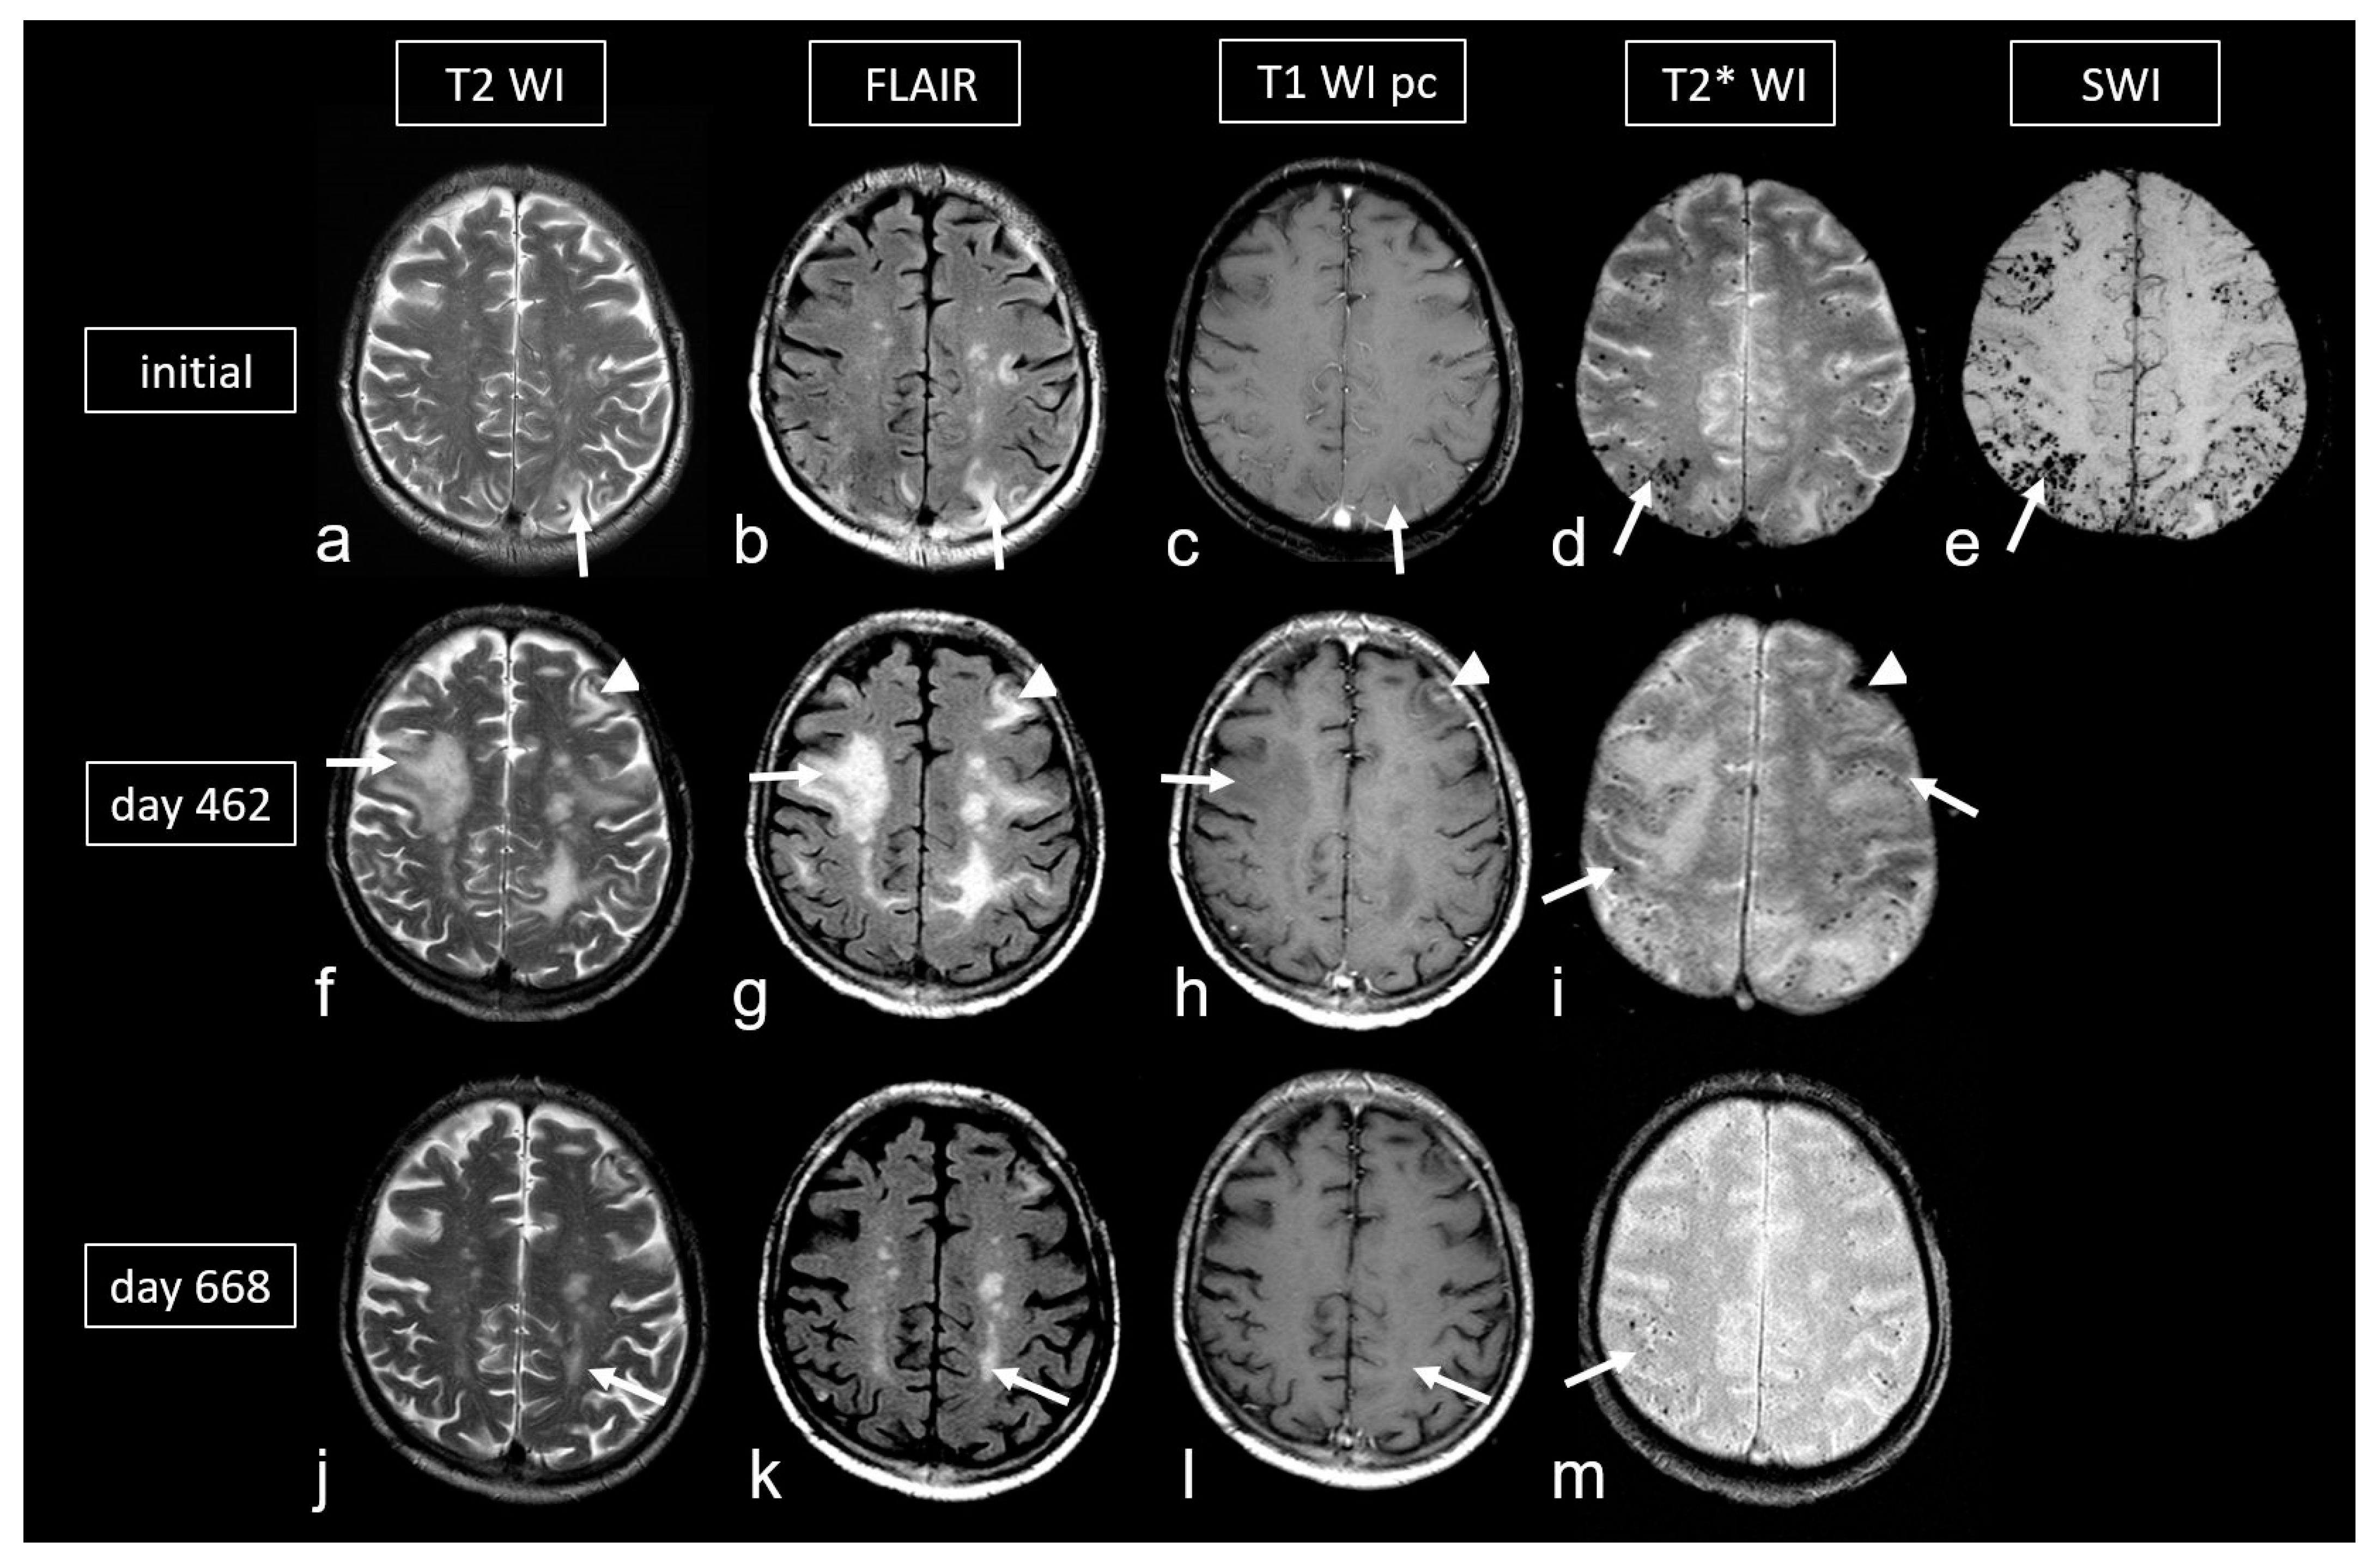

Figure 6.

Cerebral amyloid angiopathy-related inflammation (CAA- ri) in a 72-year-old man suffering from subacute deterioration of consciousness and dizziness. (a–e): Initial MRI (upper row; MRI 3.0 T Siemens Magnetom) showing several hyperintense lesions preferentially in the subcortical occipital region ((a,b): arrow) without contrast enhancement on post-contrast T1-weighted images (T1 WI pc; (c), arrow), focal-accentuated microbleeds (MB) on T2* WI ((d), arrow) and susceptibility-weighted imaging (SWI; (e), arrow); note the higher sensitivity for MB on SWI (e) compared to T2* WI (d). (f–i): MRI (1.5 T Intera, Philips Healthcare) at readmission due to subacute severe psychosyndrome after tapered corticosteroid therapy. Multiple occasionally space-occupying hyperintense white matter lesions ((f,g): arrow) without contrast enhancement ((h), arrow) and progressive bilateral MBs ((i), arrow). Note the additional subacute small left frontal intracerebral hemorrhage (ICH; arrowhead). (j–m): Follow-up MRI (1.5 T Intera, Philips Healthcare) after several bouts of intravenous high-dosage methylprednisolone showing distinct regression of white matter lesions ((j,k): arrow) without contrast enhancement ((l), arrow), no significant new hemorrhagic lesions (m).